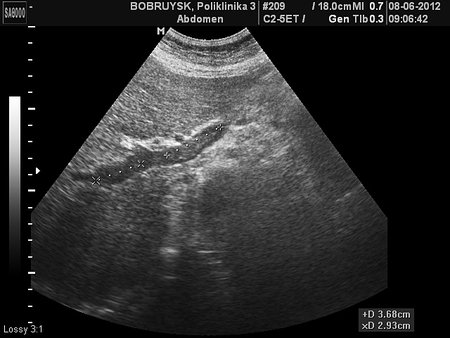

Неполный тромбоз воротной вены и ее ветвей

Женщина 62 лет.

Наблюдалась и лечилась в Минске, заключение подтверждено ангиографией там же.

- Тромбоз правой и левой ветвей воротной вены